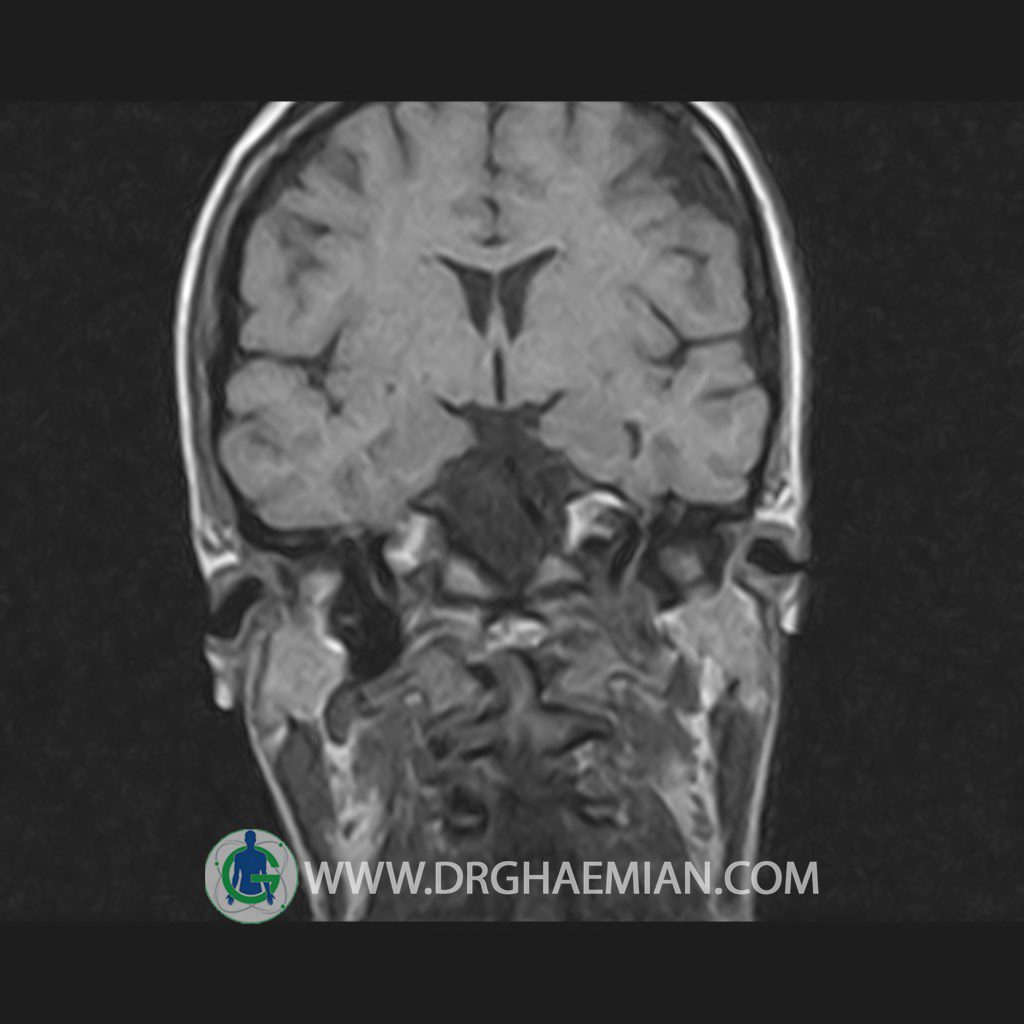

پزشکان اغلب از تصویربرداری ام آر آی برای تشخیص و درمان عارضه های پزشکی که فقط با استفاده از اشعه ایکس یا میدان مغناطیسی و امواج رادیویی قابل مشاهده است، استفاده می کنند. دستگاه ام آر آی تصاویر دقیق از ساختار های داخلی بدن ایجاد می کند. در این کیس هیپرپلازی هیپوفیز و آدنوم مشاهده می شود.

HYPOPHYSIS MRI

(with and without contrast)

Technique: Axial , coronal T1 , Axial , coronal , sagittal T2 , Axial, coronal T1 post Gd & 64 dynamic thin coronal slices.

REPORT :

The sella shows normal size , position and configuration .

The borders of its floor and walls are smooth and sharply defined .

The infundibulum is centered and of normal size .

The optic chiasm and suprasellar spaces appear normal .

The cavernous sinus and imaged portions of the internal carotid artery and carotid siphon are unremarkable .

Evaluable portions of the neurocranium show no abnormalities .

The sphenoid sinus is clear and pneumatized .

– Mild convexity at superior border of pituitary gland with post contrast homogeneous enhancement suggestive for pituitary hyperplasia & iso signal adenoma

is seen